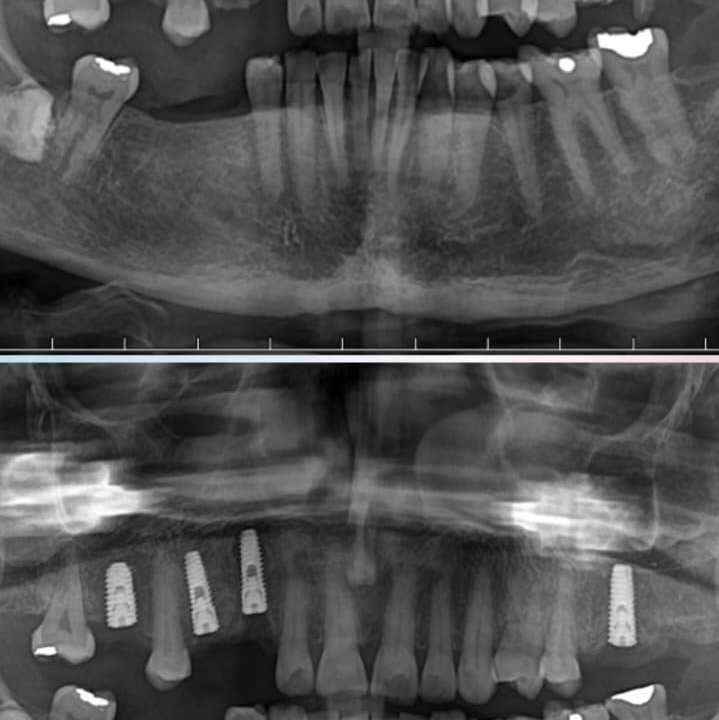

✔️ CBCT & radiographic evaluation

✔️ Bone quality & quantity assessment

🔹 Implant size & diameter based on bone mapping

🔹 Surface & design selected based on load requirements

🔹 Position planned digitally for prosthetic-driven outcomes